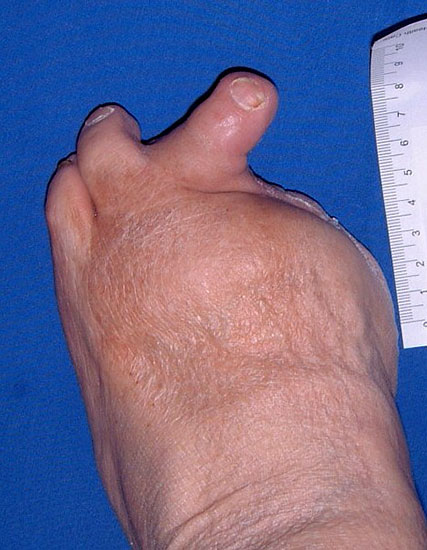

Es ist ungünstig, wenn wenige Kleinzehen lateral belassen werden. Das führt zum Kippen der Nachbarzehen oder zur Fehlstellung der verbliebenen Zehen (Abb. 18 - 20) und schließt eine optimale schuhtechnische Versorgung aus. Weitere Druckulzera sind zu erwarten. Die Großzehe kann als einzige Zehe belassen werden, wobei dann bisweilen die Arthrodese im Großzehengrundgelenk zur Stabilisierung ratsam ist (Abb. 21, 22).

Wird der Ansatz des M. fibularis (peroneus) brevis bei Amputation des 5. Strahls entfernt, kommt es durch das muskuläre Ungleichgewicht zu einer Supination mit Vorfußadduktion und nachfolgend zu einer vermehrten Druckbelastung am Außenrand des Fußes (Abb. 30, 31). Um einer chronischen Ulzeration vorzubeugen, muss die Fehlstellung beseitigt werden, meist durch Transfer der Tibialis anterior Sehne.